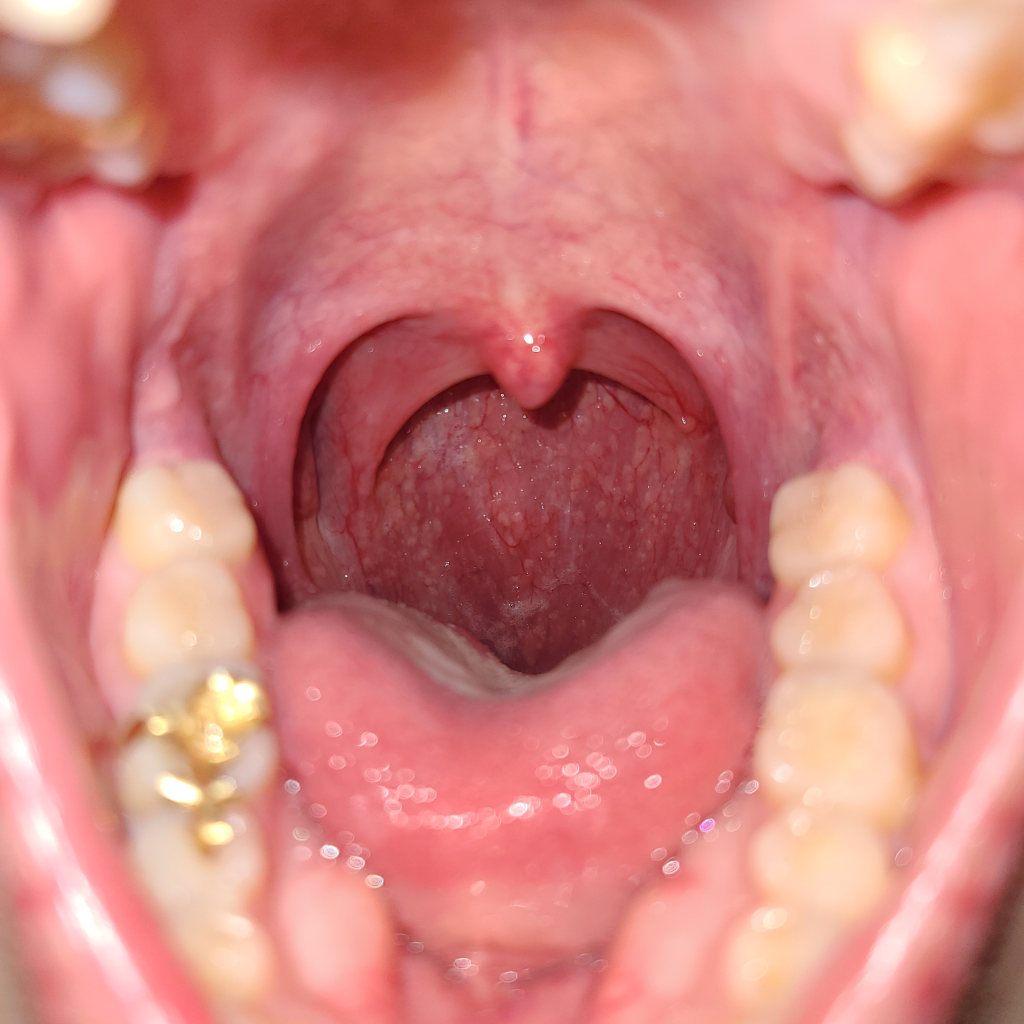

안녕하세요. 서민석 의사입니다.

정상 목 소견으로 보여요. 부어 있는 부분은 없습니다. 물론 빨갛게 되어 있어서 염증이 있다고 판단할 수도 있을 듯 합니다만, 인후염이나 역류 증상도 비슷한 결과를 보일 수는 있습니다.

명확한 부종은 관찰되지 않습니다.